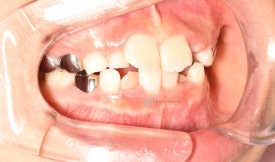

투명교정 10개월차입니다.

치료 후 - 유치 어금니들이 빠지고 영구치가 맹출하고 있습니다.송곳니가 나올 공간을 충분히 마련하며 확장하여 고른치열을 완성했습니다.